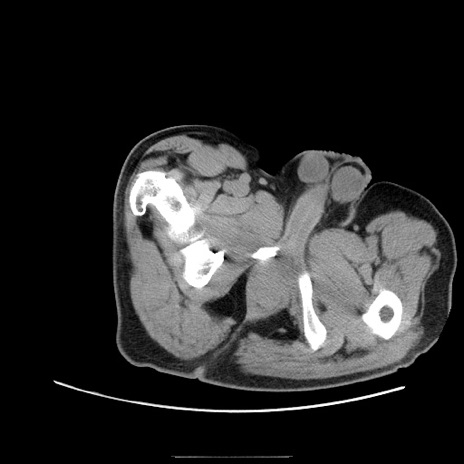

症例22(横断像)

【症例】50歳代男性

【主訴】腹痛

【現病歴】AVMからの被殻出血のため回復期リハ病棟入院中。 本日午後3時頃急に下腹部痛が出現した。

【既往歴】AVM、被殻出血、虫垂炎、高血圧

【身体所見】意識晴明、左半身不全麻痺、会話の理解は良好、36.5°C、腹部:膨隆、全体に板状硬、下腹部正中に圧痛点あり、反跳痛-、筋性防御不明、右下腹部にope scar

【データ】WBC 9400、CRP 0.06